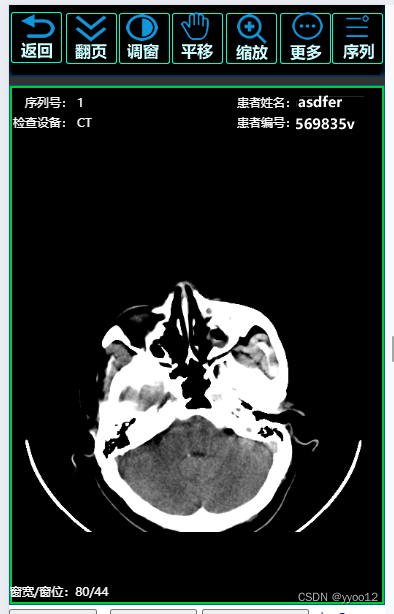

医疗影像dicom在线浏览,翻页、窗宽窗位、缩放、测量、CT值等,js直接加载文件流,整合cornerstone .js 、dicomParser.js、imageLoader.js,翻页时加载,几百张影像流畅,结合医卡,无网时本地离线使用